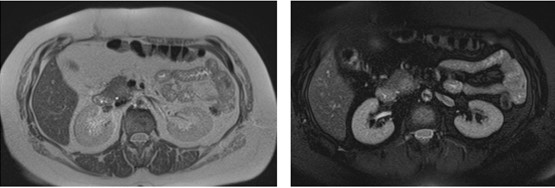

Caso 4

Paciente masculino de 35 años de edad, con antecedentes de tabaquismo, etilismo, consumo de sustancias psicoactivas. Ingresa al hospital de Sanatorio Franchin el 24 de mayo de 2024, donde se constata hipoglucemia severa con buena respuesta al glucosado hipertónico endovenoso. Al examen físico con la típica tríada de Whipple, dado por síntomas neuroglucopénicos de alteración del estado de conciencia, glucemia de 25 mg/dl y alivio sintomático después de la administración de glucosa. El paciente recupera el estado de conciencia y refiere dolor abdominal a nivel de epigastrio, por lo que se le realiza ecografía abdominal, donde se evidencia lesión nodular hipoecogénica en cuerpo del páncreas. Por esta razón se pasa al paciente a tomografía, donde se constata una formación nodular a nivel del cuerpo del páncreas, que presenta un ávido realce en fase arterial con homogeneización de la lesión en tiempo tardío.

Una vez que tengamos una fuerte sospecha diagnóstica basada en la clínica y el laboratorio bioquímico viene la localización del tumor, que se puede realizar a través de métodos no invasivos, como la ecografía, que como método de abordaje inicial no está mal para una primera exploración, pero debemos conocer que su sensibilidad es muy baja, del 9%. Pero como un estudio no invasivo, rápido, relativamente económico, y si está disponible en nuestro servicio, se puede utilizar. Los insulinomas se pueden observar por este método como una imagen nodular hipoecogénica que puede mostrar ante la presencia de Doppler color un patrón periférico o centrípeto, porque recordemos que estos son tumores hipervasculares, lo que significa que tienen una alta densidad de vasos sanguíneos.

Ahora bien, como se mencionaba al principio, el estudio ecográfico es de muy baja sensibilidad y se identifique o no la lesión por este estudio, nuestro siguiente paso en el algoritmo diagnóstico de esta lesión es la tomografía. Esta es la prueba no invasiva inicial, con una sensibilidad del 63% al 83%, y detecta del 70% al 80% de los tumores. Esta debe realizarse como un estudio trifásico: fase arterial temprana a los 30 segundos, fase venosa a los 70 segundos, fase tardía de 3 a 5 minutos. La característica de estos tumores por tomografía es que se presentan como una masa sólida que tiene un ávido realce en la fase arterial, cuyo realce se mantiene y se observa más tenue en la fase venosa y en los tiempos tardíos la lesión se homogeniza.

Para mi caso, y dando una visión general de los métodos de imagen no invasivos en esta revisión retrospectiva, solo a uno de los pacientes se le detectó la lesión por ecografía, donde se visualizó una lesión nodular hipoecogénica en el cuerpo del páncreas. A los demás pacientes se les detectó la lesión por tomografía en estudio trifásico, donde resaltan las características ya descritas por la literatura de lesiones hipervasculares con intenso realce en fase arterial, localizadas en diferentes partes del páncreas, como cabeza, cuerpo y cola.